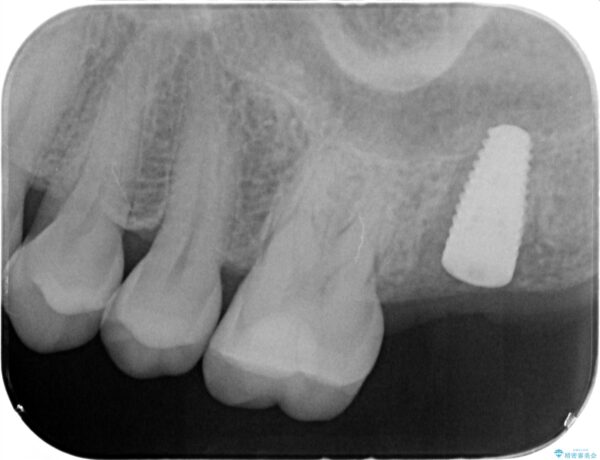

治療前

【噛むと歯が疼く】歯牙破折からのインプラント治療 治療前画像 【噛むと歯が疼く】歯牙破折からのインプラント治療 治療前画像 【噛むと歯が疼く】歯牙破折からのインプラント治療 治療前画像 【噛むと歯が疼く】歯牙破折からのインプラント治療 治療前画像 【噛むと歯が疼く】歯牙破折からのインプラント治療 治療前画像 【噛むと歯が疼く】歯牙破折からのインプラント治療 治療前画像 【噛むと歯が疼く】歯牙破折からのインプラント治療 治療前画像